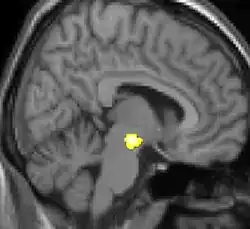

One of the first VBM studies and one that came to attention in mainstream media was a study on the hippocampus brain structure of London taxicab drivers.[7] The VBM analysis showed the back part of the posterior hippocampus was on average larger in the taxi drivers compared to control subjects while the anterior hippocampus was smaller. London taxi drivers need good spatial navigational skills and scientists have usually associated hippocampus with this particular skill.